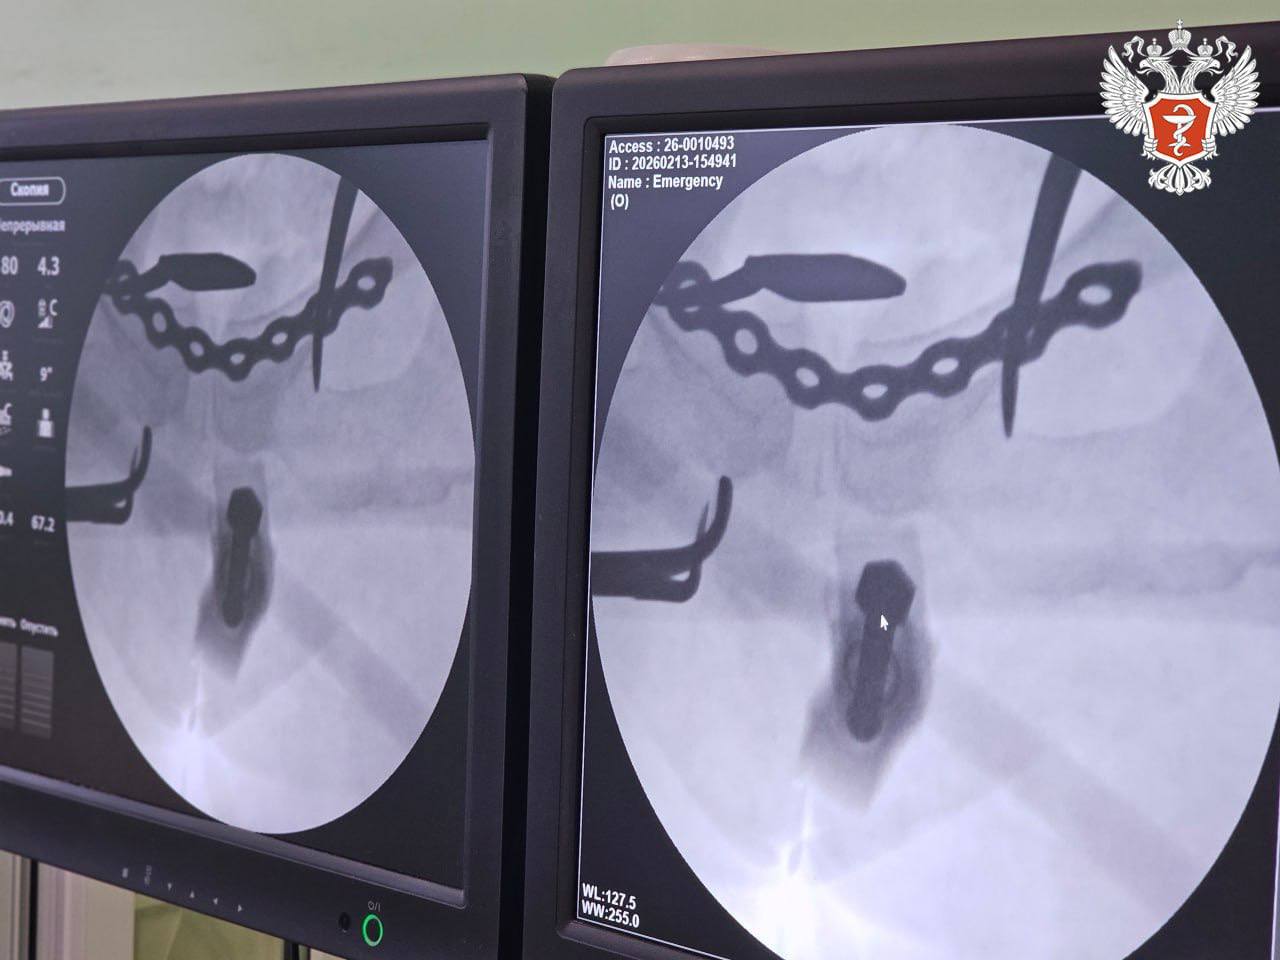

Лечение проводилось с применением аппарата внешней фиксации переломов, который позволяет быстро и малоинвазивно стабилизировать состояние пациента.

1 На первом этапе, сразу после поступления, дежурная бригада в рамках противошоковых мероприятий выполнила закрытую репозицию костей таза и их фиксацию внешним аппаратом.

Операция заняла около 20 минут и была выполнена всего через два прокола кожи, что позволило стабилизировать состояние пациентки. Вскоре женщину перевели из реанимации в профильное отделение.

2 На втором этапе врачи зафиксировали переломы: крестец укрепили канюлированными винтами через минимальные проколы, а разрыв лонного сочленения — титановой пластиной через мини-доступ.